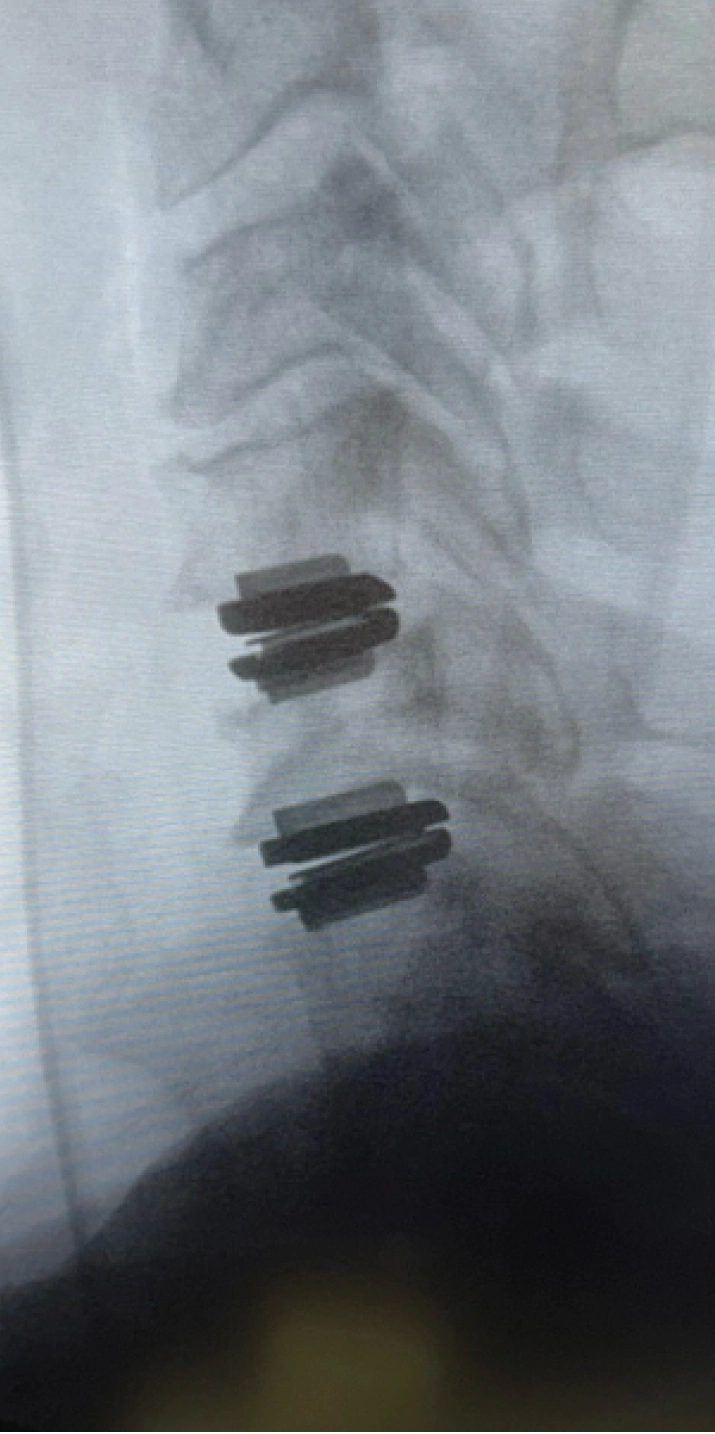

Cervical disc replacement (also called cervical disc arthroplasty) is a motion-preserving surgical procedure used to treat damaged or degenerated discs in the neck. Instead of removing the disc and fusing the vertebrae together, the damaged disc is replaced with an artificial disc implant designed to mimic natural spinal movement.

This artificial disc restores normal disc height, maintains spacing between vertebrae, and allows the neck to continue bending, rotating, and moving naturally. Unlike fusion, which permanently locks two bones together, cervical disc replacement keeps motion intact and helps reduce stress on the surrounding spinal levels.

- Using fluoroscopic guidance, the artificial disc is precisely positioned between the vertebrae to restore normal height, alignment, and mobility